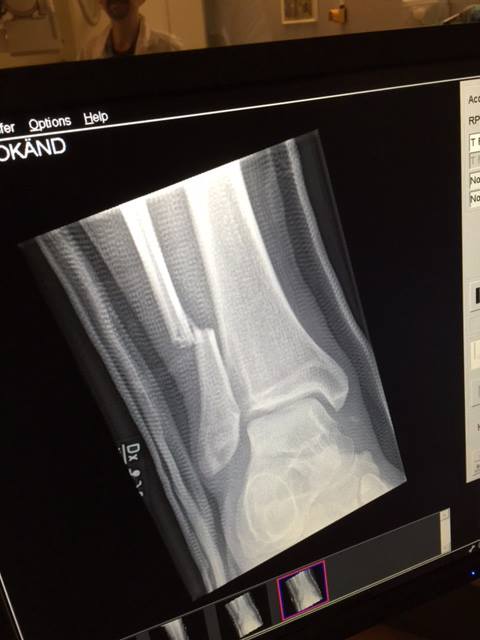

Ontem você viu aqui no TMDQA! que Dave Grohl, vocalista e guitarrista do Foo Fighters, quebrou a perna durante um show da banda na Suécia.

Mesmo com o sério problema, ele resolveu ser tratado ali mesmo no local, engessado, e continuar o show sentado com o apoio de um paramédico e até mesmo cantando de pé, com o auxílio de muletas.